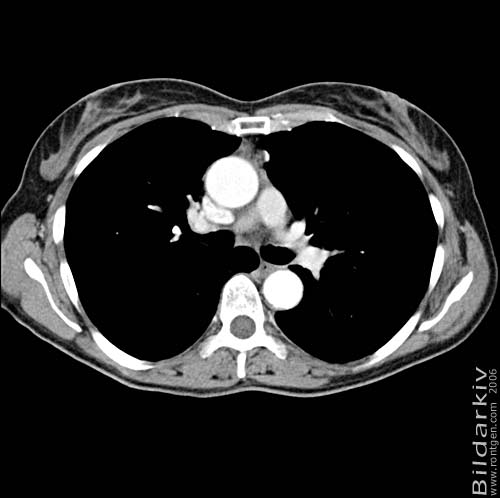

Snitt över thorax med kontrast. Sk. mediastinum-fönstersättning.

Mediastinum